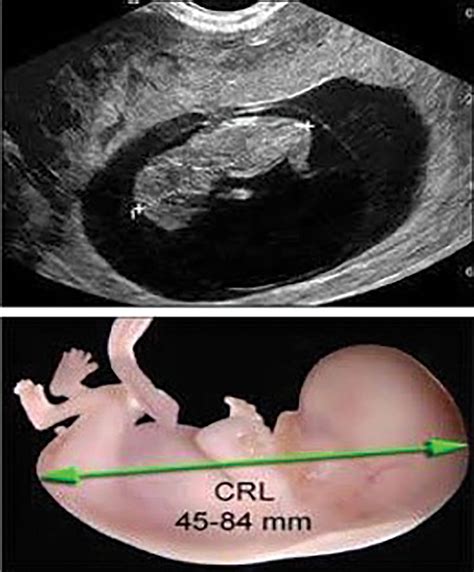

Ultrasound dating is a more precise method for determining gestational age, especially in the first trimester. It involves using ultrasound technology to measure the size of the fetus and compare it to standard growth charts. The most accurate measurements are obtained between 8 and 13 weeks of gestation.

• Transvaginal Ultrasound: This method is typically used in the early stages of pregnancy and provides a clearer image of the fetus.

• Transabdominal Ultrasound: This method is used later in pregnancy and is less invasive but may provide less detailed images.